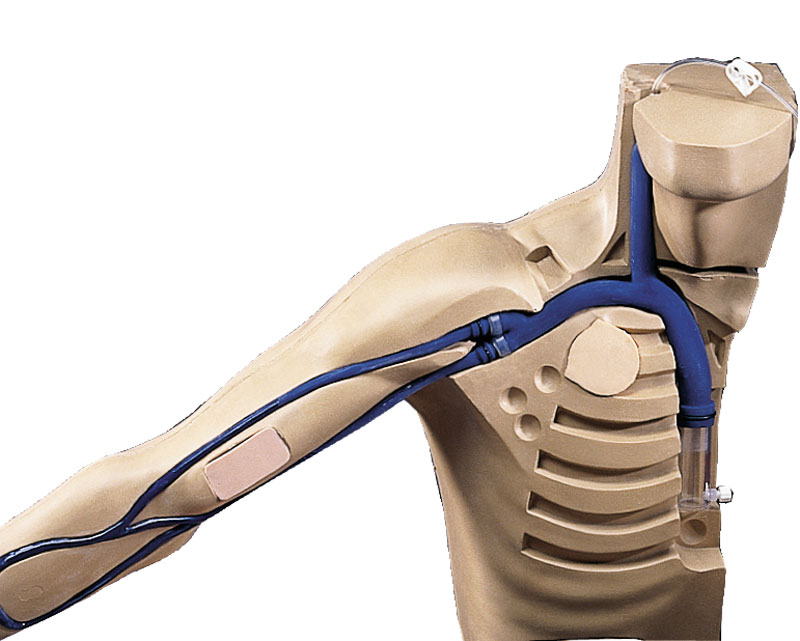

Chester Chest mit neuem, weiterentwickeltem Arm, mit Öffnung für peripherem Port

Chester Chest - mit neuem, weiterentwickeltem Arm, den Sie auch zum Aufrüsten ihres Chester Chest separat bestellen können! Chester Chest ist ein unvergleichliches Lehrmittel, das die Möglichkeit bietet, den perfekten Umgang mit folgenden Langzeit-Gefäßzugängen zu erlernen:

• Implantierter Port • Zentraler Venenkatheter (ZVK) • Peripher inserierter zentraler Venenkatheter (PICC)

Der neue, weiterentwickelte Arm verfügt über einen doppellumigen 5FR-PICC (Peripherally Inserted Central Catheter), der aus der V. basilica – dem bevorzugten Zugang – austritt. Im Bereich des PICC-Katheterzugangs befindet sich eine Aussparung zum Legen eines peripheren Ports (Dieser Port ist abgebildet, aber nicht im Lieferumfang enthalten.) Ein weiteres Merkmal des neuen Arms ist ein 20G IV-Katheter im Unterarm. Der neue, weiterentwickelte Arm verfügt über einen höheren Rotations- und Streckgrad als das Vorgängermodell und kann zum Üben von Reinigung, Anlegen von Verbänden und Fixierungen sowie Legen und Ziehen von Infusionen genutzt werden. Der rechte Brustkorbbereich ist bereits mit einem operativ gelegten ZVK (Zentraler Venenkatheter) ausgestattet. Des Weiteren können Katheter in die V. jugularis externa und in die V. subclavia durch vorhandene Öffnungen gelegt werden. Im Bereich der linken Brustkorbhälfte zeigt sich ein implantierter Port. Mittels verschiedener mitgelieferter Gewebelappen können erschwerte Zugangssituationen imitiert werden: tief liegender, gekippter und verrutschter bzw. wandernder Port. Chester Chest kann in aufrechter Haltung oder Rückenlage verwendet werden.

Lieferung mit Blutreservoirbeutel, Babypuder, Gebrauchsanweisung.